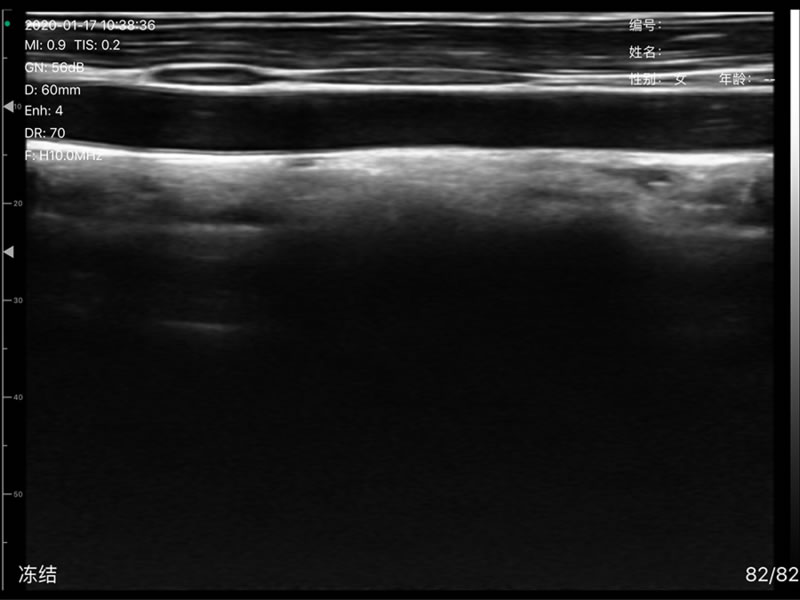

• 扫描方式:电子阵列扫描

• 探头阵元数:256

• 声头宽度:8cm

• 探头频率:7.5/10MHz

• 扫描深度:20/40/60mm,可调

• 显示模式:B、B/M、CF、PW、PDI